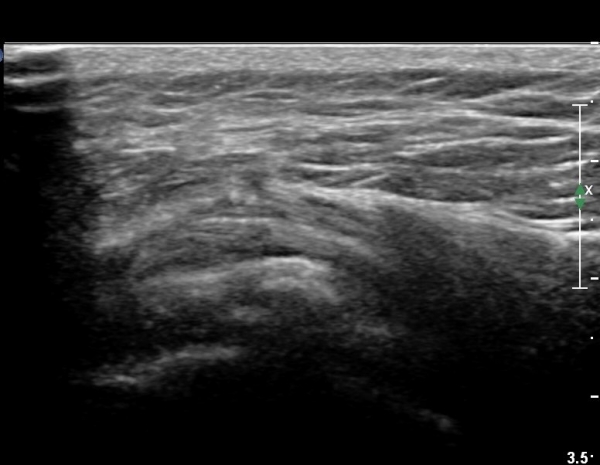

ÃÊÀ½ÆÄ °Ë»ç

Ä¡·á

Á¡¾×³¶³» ÁÖ»çÄ¡·á¿Í ¼®È¸ÀÇ ÁÖ»ç¹Ù´Ã ÀÚ±Ø(needling)